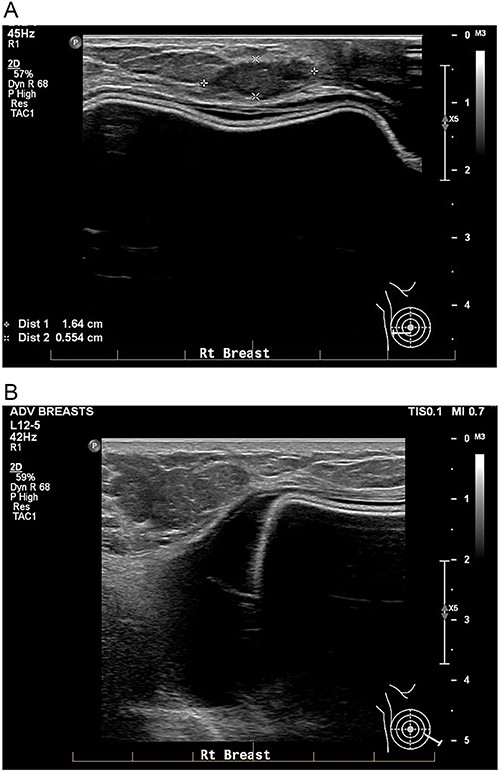

She underwent bilateral mammograms and ultrasounds of breasts and axillae (Figs 2, 3A and 3B). Within the right breast, the mammogram demonstrated a suspicious mass with two calcified foci that correlated to a 19 × 15 × 6-mm hypoechoic lesion at the 9/1 o’clock position on ultrasound. Core biopsy confirmed this to be a Grade 2 invasive ductal cancer (IDC), which was ER/PR positive and HER2 negative.

A: USS of the right breast showing a mass at the 9 o’clock position. B: USS of the right breast showing a peri-implant effusion.